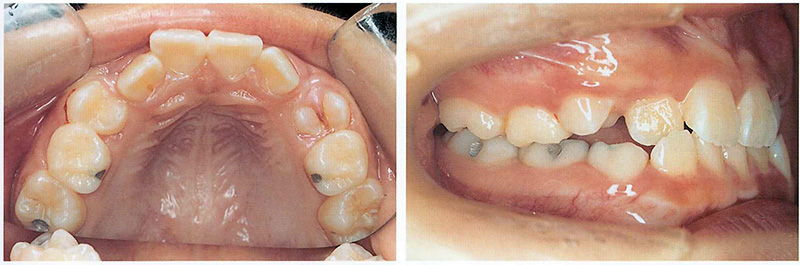

위 환자의 경우 왼쪽 송곳니가 내려올 공간은 부족하고 오른쪽 앞니도 안으로 들어가서 나와 반대로 물리고 있었습니다. 그리고 오른쪽 두번째 작은 어금니 또한 앞뒤 치아에 걸려서 내려오지 못하고 있었습니다. 물론 나중에 성인이 된 이후에 교정을 해도 되겠지만(발치 교정을 해야 할 가능성이 높아지겠죠), 커서 복잡한 치아 교정을 안해도 될 수 있도록 다른 치아들이 맹출하기 전에 미리 공간을 만들어주기로 하였습니다.

아래 사진은 위 환자와 비슷한 케이스로, 치과교정학 교과서에 나오는 사진을 발췌한 것입니다. 양측에 공간이 부족하여 나오고 있지 못한 송곳니 공간을 만들어주기 위해 sagittal appliance를 착용하였고, 그 결과 드라마틱하게 송곳니가 모두 맹출하였고 거꾸로 물리던 앞니도 교정되었습니다. 이런 가철성 장치 교정을 어렸을 때 해주지 않았다면, 커서 발치 교정을 했어야 했을 케이스였습니다.